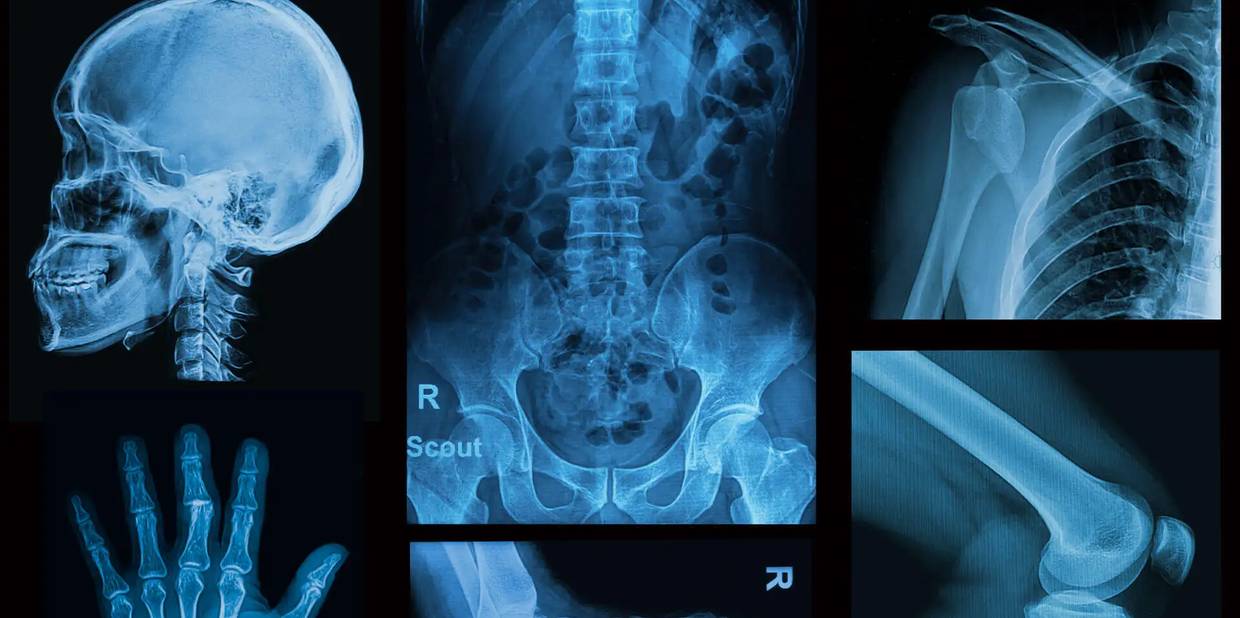

Exames como raio-x e tomografia computadorizada possuem um efeito cumulativo e aumentam a chance de câncer por radiação, principalmente em crianças. (3) As punções venosas para coleta de sangue parecem inofensivas, mas um estudo recente mostra que 52% de pessoas apresentaram complicações, sendo que 5% das complicações foram consideradas seríssimas e precisaram de intervenções cirúrgicas. (4)